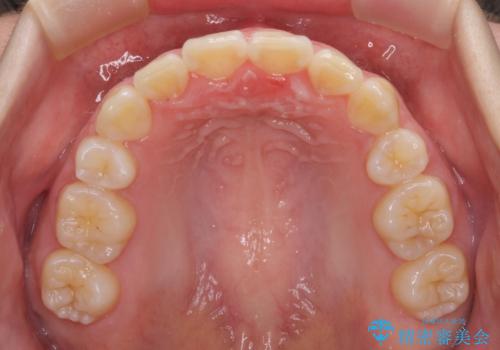

歯列はきれいに整いますが、歯肉ラインは治療前の歯肉の位置を踏襲します。

特に八重歯であった歯は歯冠が長く見えますので、改善を希望される場合には、歯肉移植術を行う必要があります。